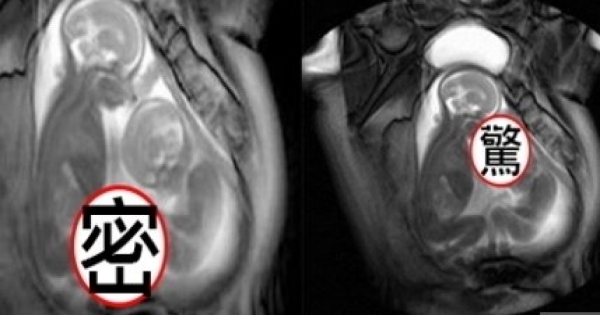

驚呆!雙胞胎在媽媽肚子打架全記錄!只見弟弟用腳不斷攻擊哥哥!

接下來要看的影片,是一對親兄弟在媽媽肚子裡面發生的情形。大家可能以為雙胞胎的感情特別好,但其實不是!他們打從娘胎的時候,就開始會互相玩耍跟打架了!我們一起來看看這個生命的奇蹟吧!

▲大家都以為在羊水裡的小貝比是這樣的情形。

但事實上其實是.......打架!